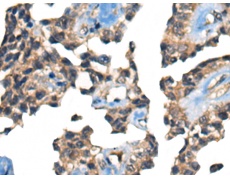

IHC positive control: |

Human ovarian cancer |

IHC Recommend dilution: |

25-100 |